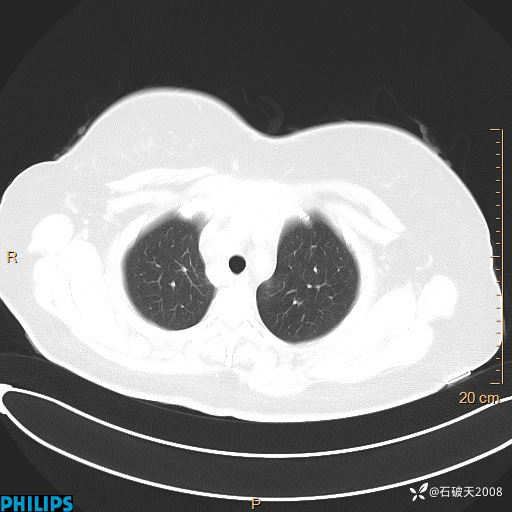

肺结节病?纵膈型肺癌?淋巴瘤?有点意思,欢迎围观

女 52岁 主 诉:咳嗽10余天,咳痰2天。

现病史:10余天前无明显诱因出现咳嗽,呈阵发性干咳,伴咽喉部发痒,无咽痛,无咳痰,无鼻塞、流涕、打喷嚏,无发热、畏寒、寒颤,无头痛、头晕,无胸闷、胸痛,无反酸、烧心,无腹痛、腹泻,无尿频、尿急,无皮疹等,在当地诊所求治,给予口服药物治疗(具体不详),病情无好转。遂在当地社区卫生服务中心开具口服药物治疗(具体不详),疗效欠佳。2天前出现咳痰,在我院门诊求治,行胸部CT提示肺部感染,建议住院,患者要求口服药物治疗,目前仍咳嗽、咳白色粘痰,白天量多,夜间自觉喉部喘鸣音,遂再次来院就诊,以“肺部感染”为诊断收入院。发病以来,神志清,精神可,饮食可,夜间睡眠差,大小便正常,近期体重无明显变化。

肺窗